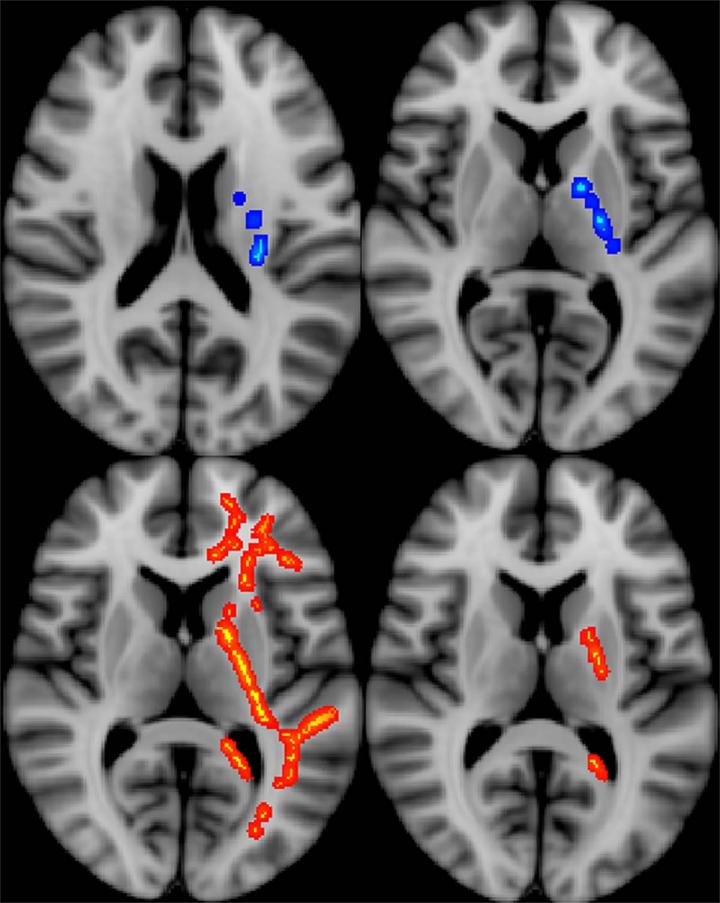

OAK BROOK, Ill. - Diffusion tensor imaging (DTI), a type of MRI, may be able to predict functional post-deployment outcomes for veterans who sustained mild traumatic brain injury (MTBI), or concussion, during combat, according to a new study published in the journal Radiology .

DTI uses measurements of water movement in the brain to detect abnormalities, particularly in white matter. Previous studies have linked DTI metrics to neurocognitive function and short-term functional outcomes in groups of patients. The desire to uncover possible long-term effects spurred Jeffrey B. Ware, M.D., from the Philadelphia VA Medical Center in Philadelphia, Pa., to evaluate combat veterans using this technique.

Dr. Ware and colleagues used brain MRI and DTI to study 57 military veterans who had a clinical diagnosis of MTBI upon return from deployment. The average length of time between injury and post-deployment evaluation was 3.8 years with an average follow-up duration of 1.4 years.

"All conventional MR images were interpreted as normal," Dr. Ware said. "We retrospectively analyzed the data from the DTI sequence to derive measures of white matter integrity, which we compared to clinical measures and subsequent outcome measures 6 months to 2.5 years after the initial evaluation."

The results showed significant associations between initial post-deployment DTI measurements and neurobehavioral symptoms, timing of injury, and subsequent functional outcomes. The measurements also correlated with greater healthcare utilization among veterans with MTBI.

Following initial post-deployment evaluation, 34 of the study participants returned to work. Veterans who did not return to work displayed significantly lower fractional anisotropy (FA) and higher diffusivity in a specific brain region, the left internal capsule. These measures imply less structural integrity in that area of the brain. As this region is known to contain important fibers providing motor stimulation to the typically dominant right side of the body, the results may provide a correlation between impairments in fine motor functioning and inability to return to work.

"Our findings suggest that differences in white matter microstructure may partially account for the variance in functional outcomes among this population. In particular, loss of white matter integrity has a direct, measurable effect," Dr. Ware said. "It was illuminating to see the association between measures of white matter integrity and important outcomes occurring months to years down the road in our study population."